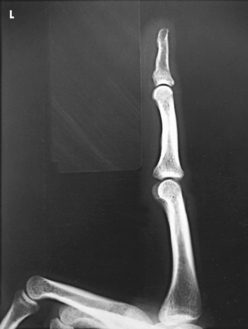

The interphalangeal (IP) articulations between the phalanges are synovial hinge type and allow only flexion and extension (Fig. 4-8). The IP joints are named by location and are differentiated as either proximal interphalangeal (PIP) or distal interphalangeal (DIP), by the digit number, and by right or left hand (e.g., the PIP articulation of the fourth digit of the left hand) (Fig. 4-9, A and B). Because the first digit has only two phalanges, the joint between the two phalanges is simply called the IP joint.

Structures shown: A lateral projection of the affected digit is shown (Figs. 4-24 through 4-27).